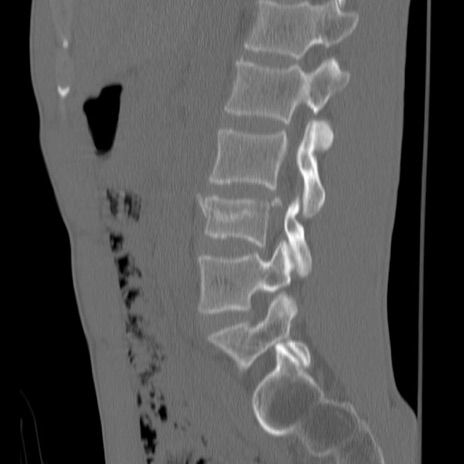

症例3 腰椎CT(矢状断像)

【症例】30歳代男性

【主訴】腰痛

【現病歴】本日旅行先で観光中に、友人と衝突し転倒し受傷。

【身体所見】麻痺なし、右下腿内側前面外側、左下腿内側に知覚鈍麻・しびれ

異常所見と診断は?

腰椎CT